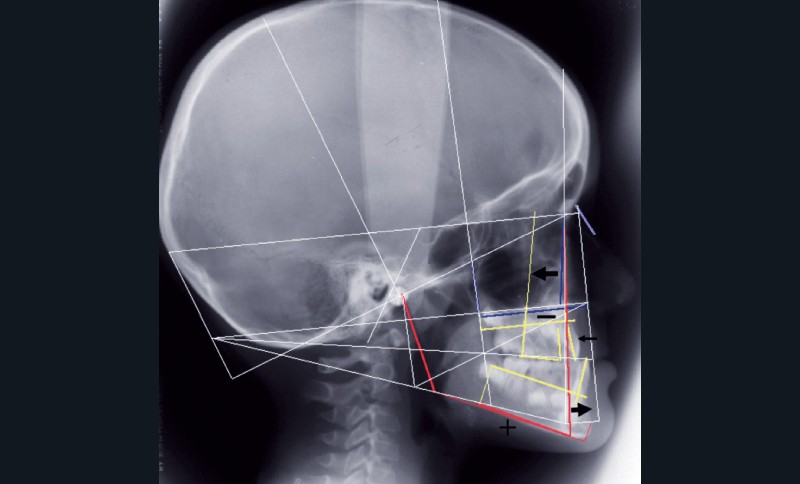

Le bilan radiographique (fig. 6) par l’analyse architecturale de Delaire et l’analyse dento-squelettique confirme l’examen clinique et conduit au diagnostic radiologique suivant :

• pas de prédisposition de la base du crâne à la classe III,

• rétromaxillie,

• brachymaxillie avec petite brachyprémaxillie,

• linguoversion incisive maxillaire,

• légère prognathie mandibulaire par dolichocorpie.